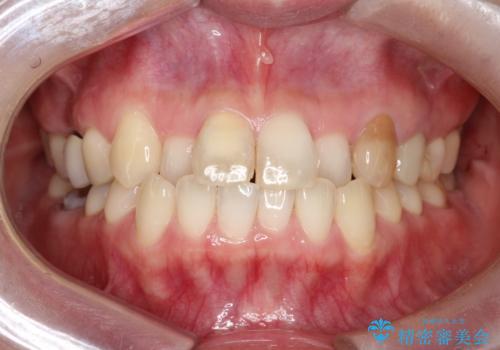

【オールセラミック】前歯の色を変えたい。

- 前歯の色が変色してきたことを主訴に来院されました。

根管治療から被せものまで治療を行いました。